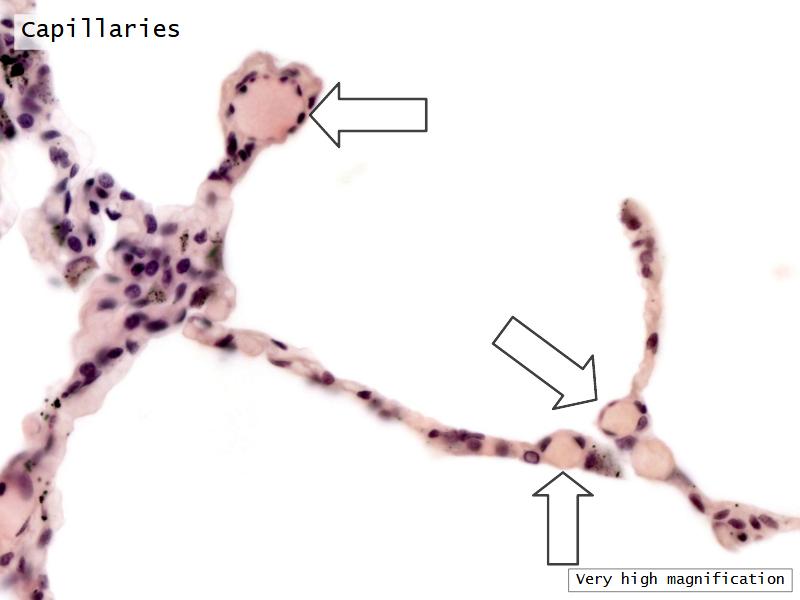

Components of the Blood-Air Barrier?

- Alveoli

Lungs